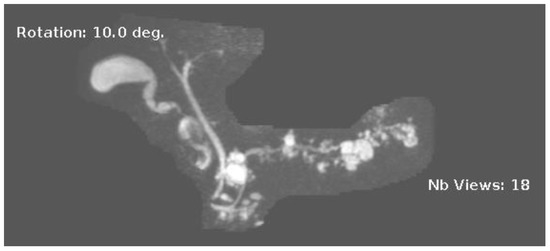

Figure 3.

MRI image of side branch IPMN.